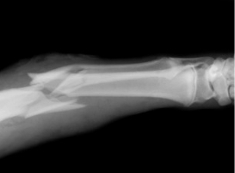

pediatric orthopedic trauma

Our physicians provide 24/7 coverage in Dayton Children’s emergency department and level 1 trauma center for patients with traumatic injuries who need orthopedic surgery.

- Fractures / broken bones

All of our pediatric orthopedic fracture clinics offer complete casting services and on-site crutch training. We treat thousands of fractures a year.